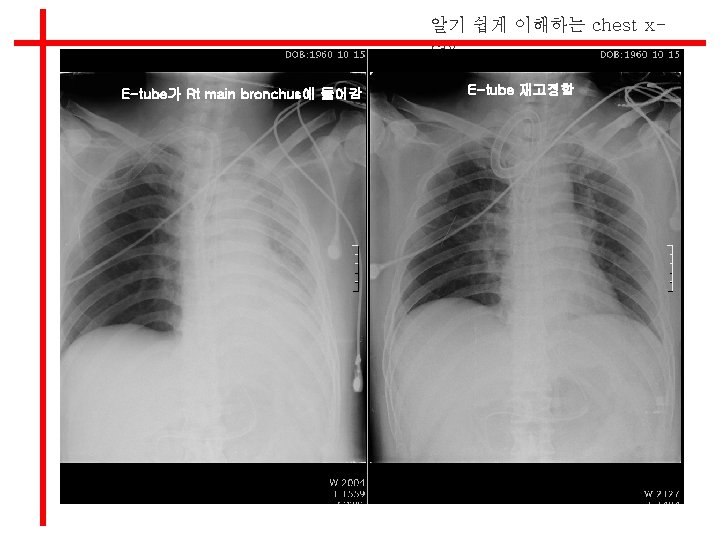

알기 쉽게 이해하는 chest xray E-tube가 Rt main bronchus에 들어감 E-tube 재고정함